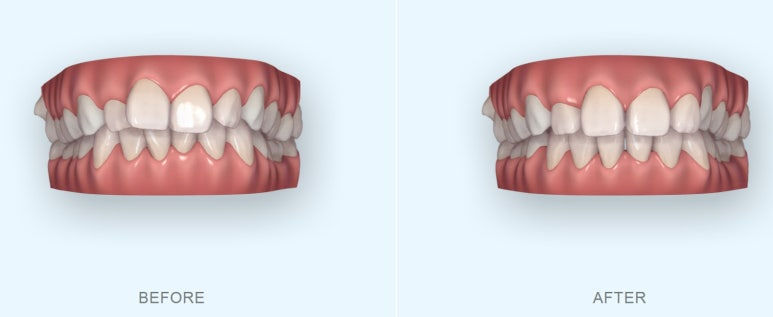

특히나 부분교정은 실현 가능성이 있는지에 대한 예측이 중요한데요.

눈대중으로 가능하겠거니 하고 들어갔다가는 결과물이 제대로 나오지 않아 만족도가 떨어지는 경우가 있어요.

그래서 치료계획에 따라 미리 가상을 시뮬레이션을 해보고 치료결과를 예측해본 뒤 실제 교정을 하게 됩니다.